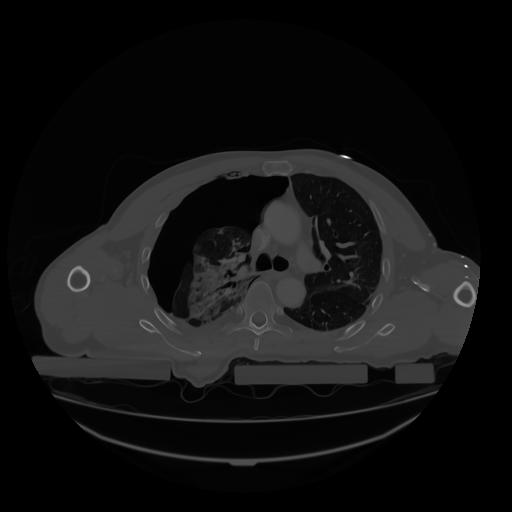

28 CUERPO,CE,Vol,2.0,CUERPO,,